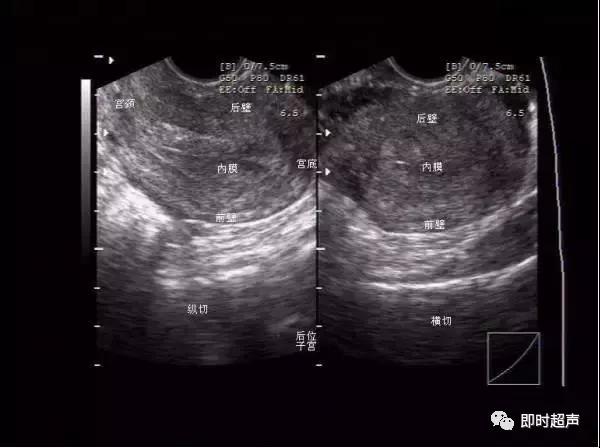

图像方位的确认

双侧卵巢的显示,与腹式超声比较,内部结构明显清晰。图片上可见数个未成熟卵泡。